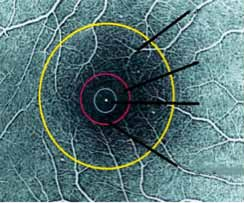

• IRM cérébrale et médullaire :

L’IRM cérébrale de début répondait aux critères de Barkhof chez 119 patients soit 94%. L’IRM médullaire faite chez 49 patients a montré des anomalies chez 35 patients (71%), et était normale chez 14 patients (29%). L’IRM cérébrale de contrôle réalisée 03 mois après l’IRM de référence faite chez 101 patients a

confirmé la dissémination temporelle chez 55 patients (54,45%), avec l’apparition de nouvelles lésions T2 chez 39 patients (38%) avec de nouvelles lésions actives chez 26 patients (25%).

Dans notre étude, aucune association n’a été retrouvée entre l’âge, le sexe, la présence de BOC et la survenue d’un 2ème événement clinique. Alroughani et al. [23] ont rapporté que l’âge de début jeune était un facteur prédictif de la survenue d’un 2ème événement dans les 2 ans. Concernant la présence de BOC, aucune différence significative n’a été retrouvée entre la présence ou l’absence de BOC et le délai de survenue d’un 2ème événement dans 2 études récentes [20,21]. Beghdadi [15] a retrouvé dans son étude que tous les paramètres IRM (le nombre de lésions T2, la topographie et l’activité lésionnelle), avaient une valeur prédictive positive dans la conversion du SCI en SEP selon les critères de Mc Donald, augmentant significativement le risque d’une deuxième poussée. De ce fait, l’IRM est actuellement l’outil le plus puissant pour prédire la conversion en SEP cliniquement définie [34].

Dans notre travail comme dans l’étude de Beghdadi [15], l’IRM cérébrale de début était pathologique dans tous les cas et répondait aux critères de Barkhof chez 94% des patients. Un peu plus de la moitié de nos patients (54,45%) se sont convertis en SEP radiologique à leur 2ème IRM de contrôle réalisée 3 mois après l’IRM de référence, dont 38% avaient de nouvelles lésions T2 et 25% avaient de nouvelles lésions rehaussées après injection de gadolinium.